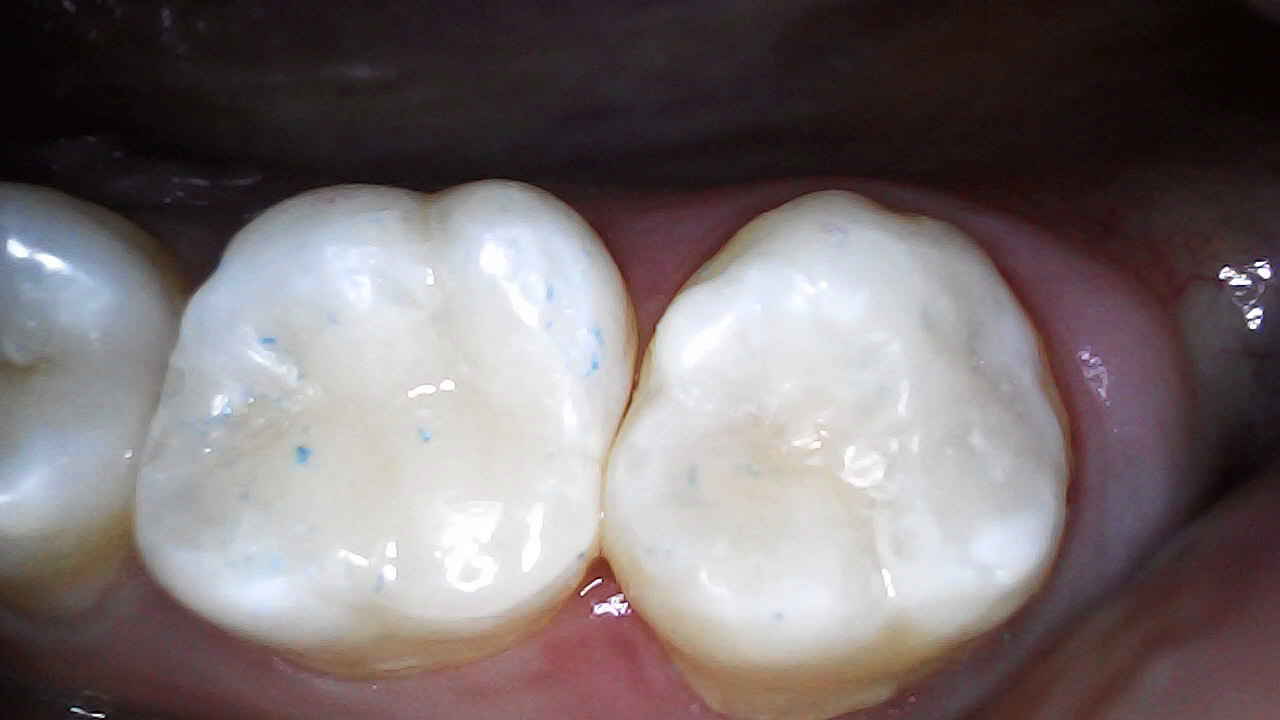

Composite restoration 37 and 36